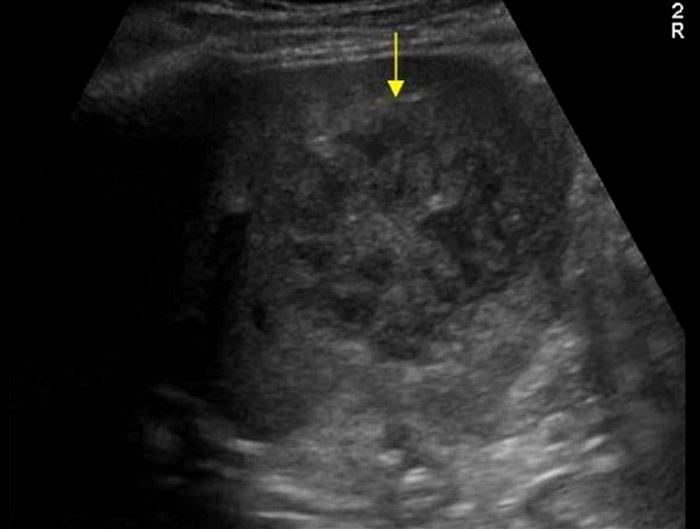

Echinococcal Cyst

Sheep Herders

AKA Hydatid Cyst

Sheep herder

Echinococcal Cyst

Sheep Herders

AKA Hydatid Cyst

Water lily

Sheep herder

Echinococcal Cyst

Sheep Herders

AKA Hydatid Cyst